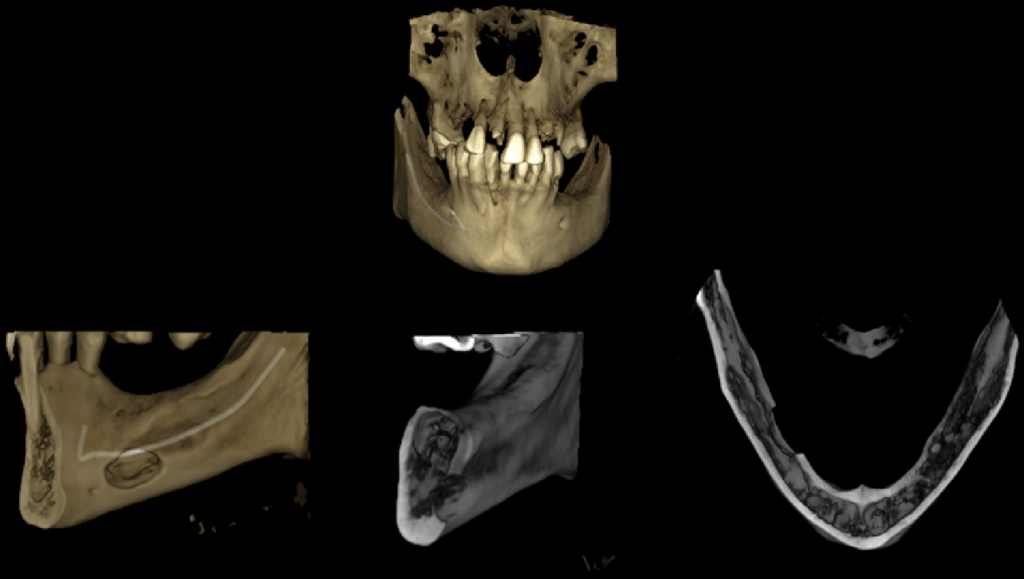

A la evaluación de la tomografía computarizada de campo mediano se observa en cortes axiales la misma imagen efectivamente parcialmente corticalizada, y que ocasiona la perdida de continuidad sólo de la tabal ósea lingual, a pesar de que en los cortes tangenciales de vestibular a lingual se asemejaría a la forma de una lesión quística en formación que se encuentra en contacto con el reborde basal, también notamos que respeta la cortical del conducto dentario inferior, finalmente en los cortes transaxiales y en la reconstrucción 3D podemos tener una mejor visión de la cavidad que no posee características patologícas y las estructuras óseas y dentarias adyacentes que no presentan alteración aparente.

RECONSTRUCCIÓN 3D